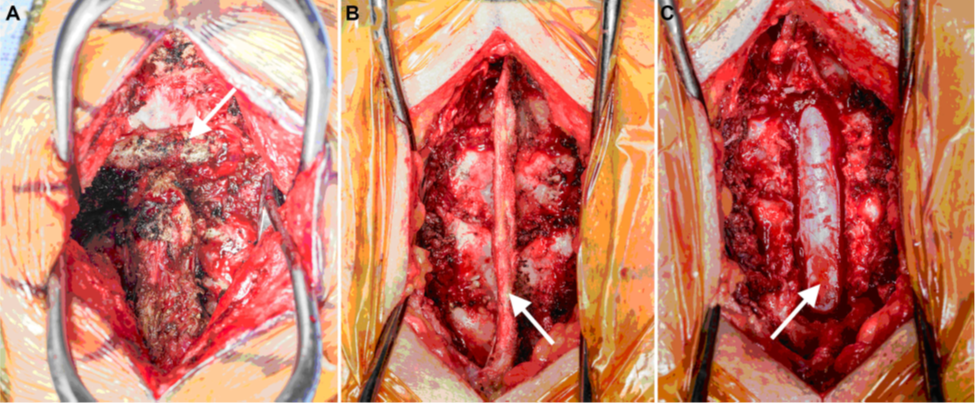

Mục đích của phẫu thuật là nhằm giảm sự mất vững của cột sống, ngăn ngừa biến dạng, và phục hồi hoặc ngăn ngừa khiếm khuyết thần kinh do chèn ép tủy sống và/hoặc rễ thần kinh (hình 4). Đường mổ nói chung gồm: trước, bên, sau, hoặc kết hợp, tùy thuộc vào vị trí tầng nào của đốt sống.

Hình 4. Phẫu trường mổ cột sống: A. Đường mổ ở cột sống cổ lối sau, tách cơ, bộc lộ các mỏm gai đốt sống cổ ở đường giữa, mũi tên chỉ nền của xương chẩm. B. Đường mổ ở đốt sống ngực lối sau, tách cơ, bộc lộ bản sống, mỏm gai và dây chằng gian gai (mũi tên). C. Cắt bỏ mỏm gai, bản sống để giải ép tủy sống (mũi tên).